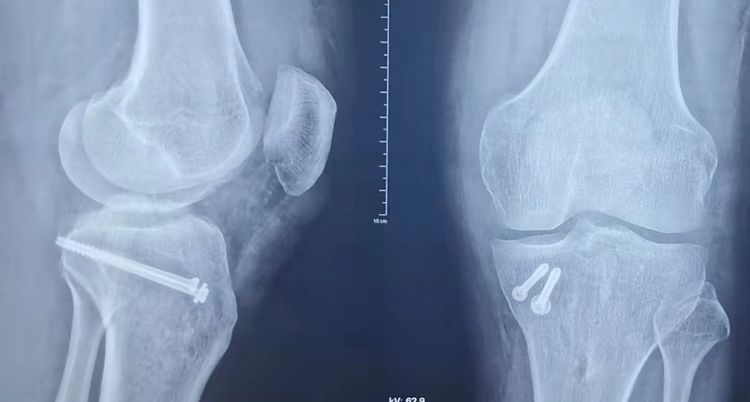

术式:左膝关节镜检+左膝关节清理+ACL胫骨止点撕脱骨折复位固定+胫骨平台骨折闭合复位空心钉内固定。

术后复查:骨折复位良好。